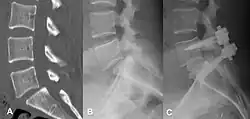

Degenerative spondylolisthesis at L5-S1.

(A) CT sagittal view of a low grade slip.

(B) Lateral radiograph pre-operative intervention.

(C) Surgically treated with L5–S1 decompression, instrumented fusion and placement of an interbody graft between L5 and S1.

Both minimally invasive and open surgical techniques are used to treat anterolisthesis.[49]